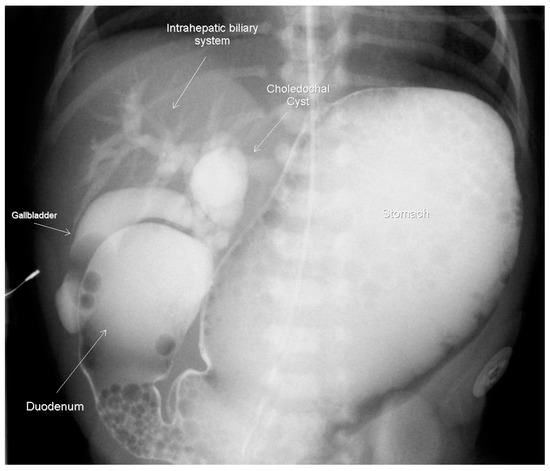

Figure 2.

Upper GI contrast study on day-of-life 2, demonstrating the duodenal obstruction with reflux into the dilated biliary tree and a choledochal cyst approximately 14 × 10 mm.